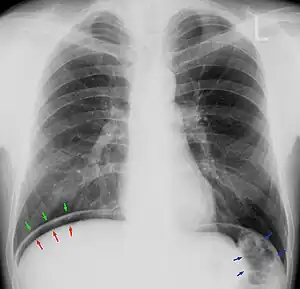

Chest X-ray with air between the right diaphragm and the liver (green and red arrows). Air also visible below the diaphragm on the persons left. Blue arrows mark a normal gas filled colon.